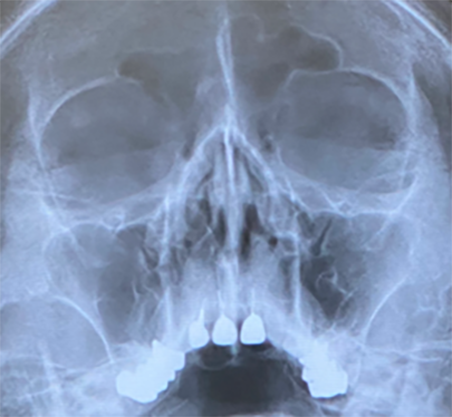

X線写真:Waters法(後頭おとがい法)

右上顎洞は正常、左上顎洞は軽度の粘膜肥厚を認め、含気もあり、軽症の上顎洞炎と診断される。